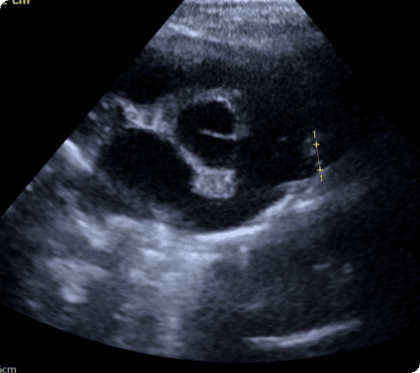

CT 혈관조영, 심장초음파 등 고사양 영상장비를 활용하여

혈관 구조와 병변을 정밀 분석, 최적의 수술 계획을 수립

간문맥단락은 간으로 가야 할 혈액이 전신으로 우회하는

비정상 혈관.

해독되지 못한 물질이 퍼져 발작 등 신경 증상을 유발하며,

조기 진단과 수술 교정이 필수적임.